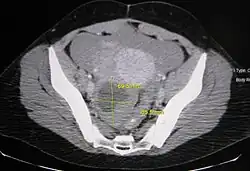

Ovarian cysts are usually diagnosed by pelvic ultrasound, CT scan, or MRI, and correlated with clinical presentation and endocrinologic tests as appropriate.[15] Ultrasound is the most important imaging modality, as abnormalities seen in a CT scan sometimes prove to be normal in ultrasound.[5][8] If a different modality is needed, then MRIs are more reliable than CT scans.[5]

Ovarian cysts are considered large when they are over 5 cm and giant when they are over 15 cm. In children, ovarian cysts reaching above the level of the umbilicus are considered giant.

Risk of cancer

Accurately differentiating an cyst from a cancer is critical to management. Medical imaging showing a simple, smooth bubble of watery liquid is characteristic of a benign cyst.[8] If the cyst is large, is multilocular, or has complex internal features, such as papillary (bumpy) projections into the cyst or solid areas inside the cyst, it is more likely to be cancerous.[13]